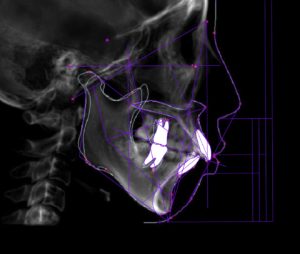

矯正治療前

赤い線が切端ライン

青い線が歯頚部ラインです。

抜歯後8カ月経過

唇側に向いていた切端ラインが

抜歯後内側(口蓋側)に向いています。

このように前歯を後退できるのは

精密検査時のCTデータで

骨の厚み、歯根の位置を立体的に把握し

前歯を下げても骨や歯肉に無理が生じないことを

事前に確認した上で治療を行うからです。